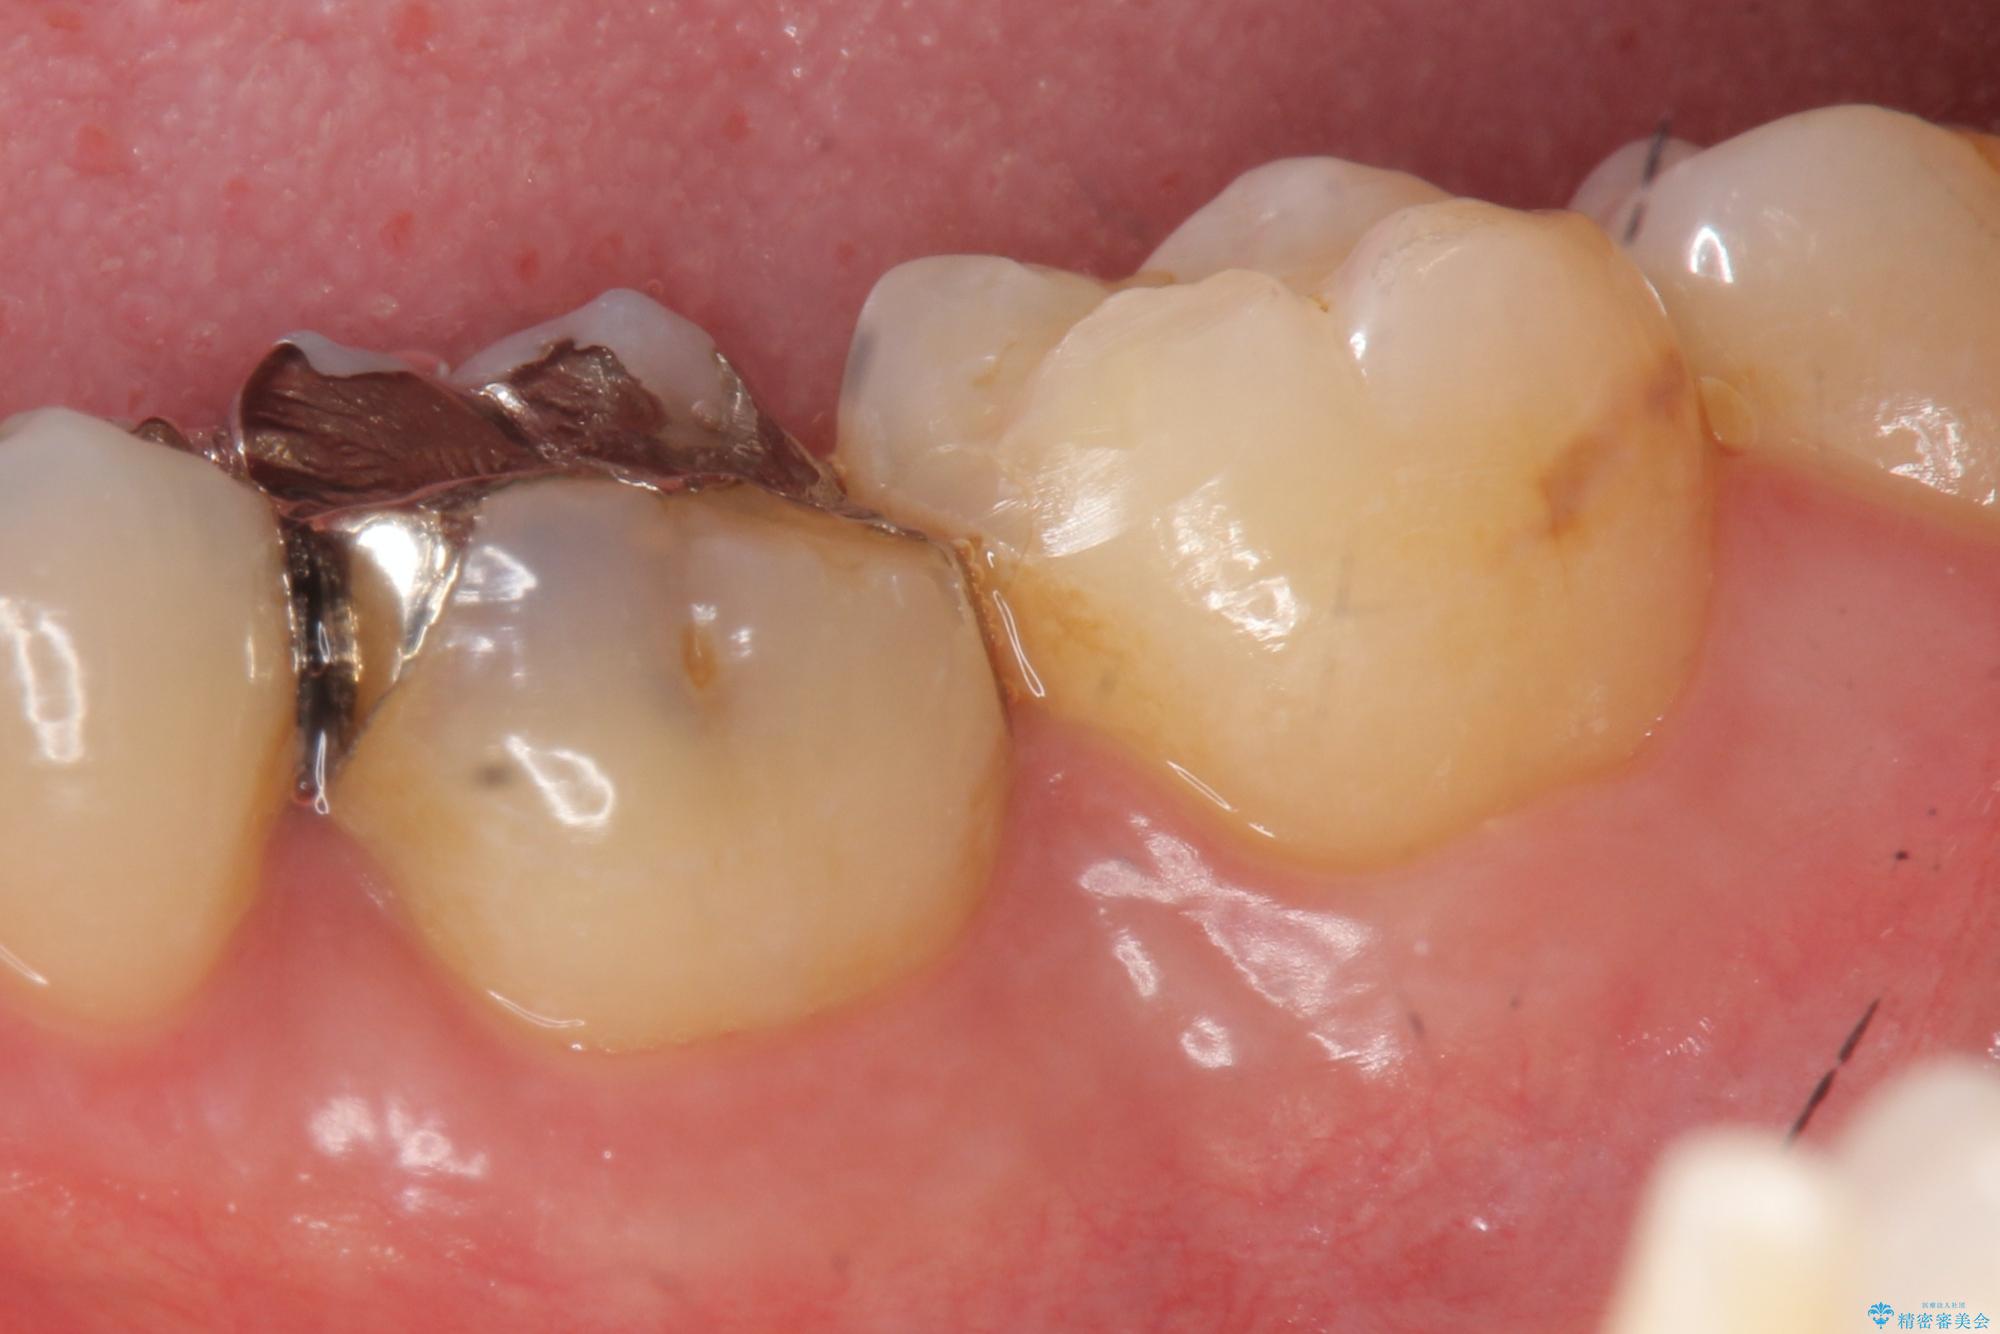

食べ物がよく詰まる、見た目も悪いので銀歯をやり替えたいとご来院された患者様です。

治療計画

銀歯の適合や形態不良により、食べ物が非常に挟まりやすく、虫歯の再発も銀歯の下に認められる状態でした。

不適合な修復物、虫歯の除去を丁寧におこなったのち、清掃しやすい形態へと回復する精密なセラミック治療を行います。